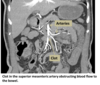

Which vessel is most commonly involved in acute mesenteric arterial embolism?

Superior mesenteric artery (SMA)

- Multidetector CT: if SMA occlusion suspected